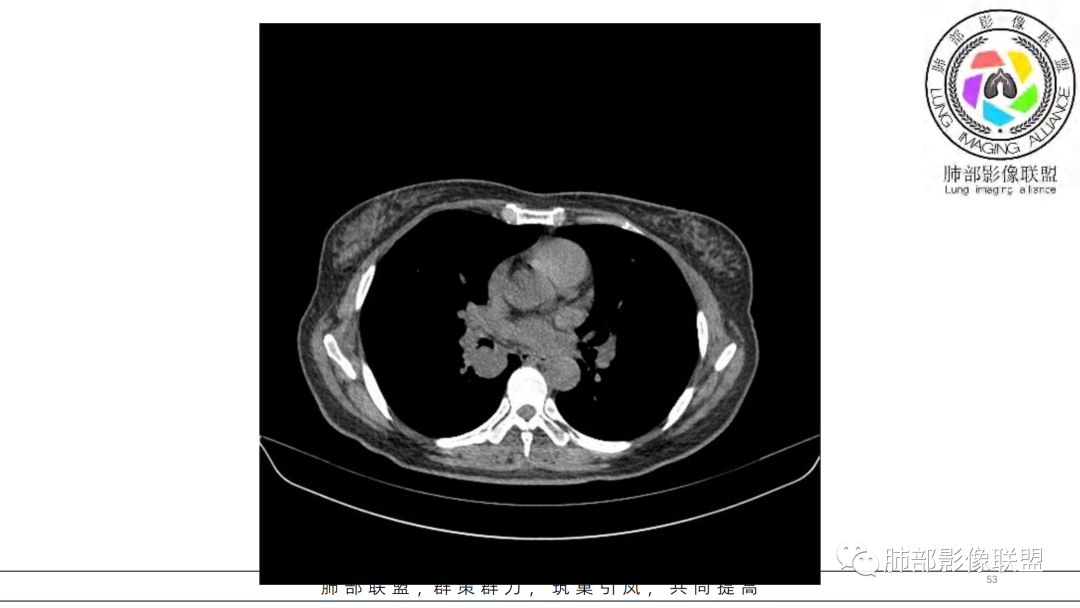

2.右肺下叶及中间段支气管后方类圆形块影,边界较清楚,未见分叶及毛刺,病灶部分突入支气管腔内(冰山一角),局部管腔狭窄,相应肺叶未见片影或体积变化。

3.块影密度均匀,未见液化坏死及钙化,渐进性强化,强化显著。

综合分析:

中青年女性,支气管管腔内外肿块(“冰山征”),边界较清楚,强化显著,未见阻塞性肺不张,尽管未出现“类癌综合征”临床表现,仍然符合典型类癌影像学表现。

类癌临床表现无特异性,影像学检查仍然是肺类癌的主要诊断依据。其特征性表现是孤立的、边界清楚的肿物,密度可均匀或不均匀,边缘多清楚锐利,部分病例可见浅分叶及毛刺。类癌侵及的支气管局部增厚,与正常的管壁分界清楚,局部呈乳头状突起,表面光滑。肺门旁肿块往往边缘光整、轮廓清楚、密度均匀,增强扫描大多呈均匀明显强化,可有持续强化或延迟强化。中央型肺类癌可引起支气管壁局限性增厚,形成轮廓光滑的管壁结节,并与腔外大病灶形成“冰山征”。少数病例可沿支气管腔内长轴生长,呈指套样改变,类似肺鳞癌,但较肺鳞癌血供丰富。